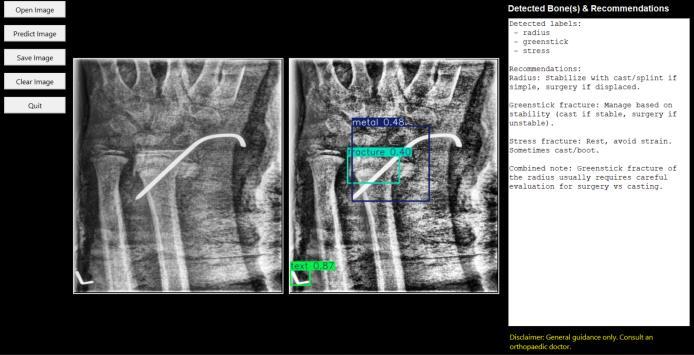

After preprocessing, the enhanced X-ray image is passedtotheYOLOv8(YouOnlyLookOnceversion8)deep learning model. YOLOv8 is a powerful object detection algorithm capable of performing real-time detection with high accuracy. The model is trained on a custom dataset containing X-ray images annotated with fracture regions. Whenanimageisprocessed,YOLOv8detectsthepresenceof fractures and marks them with bounding boxes. Each bounding box includes a label that specifies the detected fracture and a confidence score representing the model’s certainty.TheYOLOv8modelisdesignedtodetectmultiple types of fractures, such as transverse, oblique, and compound fractures, and can also identify which bone is affected,suchasthefemur,tibia,orhumerus.Thedetection resultsarevisualizedontheX-rayimage,makingiteasierfor the user to understand the location and severity of the fracture.

Thefinalmodulefocusesonmappingthedetected fracturestospecifictypesandaffectedbones,andproviding generalmedicalrecommendations.OncetheYOLOv8model identifiesafracture,thesystemmapsthedetectionresultsto a set of predefinedclassifications thatdescribe the typeof

fractureandtheboneinvolved.Basedonthisclassification, the system generates a treatment recommendation by referringtoamedicalknowledgebasecontainingstandard guidelines. For instance, a simple transverse fracture may require immobilization using a cast, while a compound fracturemayneedsurgicalintervention.Thesystemdisplays these recommendations in the graphical interface for user reference. A medical disclaimer is also included, clearly stating that these recommendations are for guidance only andthatusersmustconsultahealthcareprofessionalforfinal diagnosisandtreatment.TheGUIprovidesasimpleinterface to display the processed X-ray image with the detected fracture, classification details, and recommended treatmentoptions.

The Bone Fracture Detection System using YOLOv8 successfullydetectsandclassifiesfracturesinX-rayimages withhighaccuracy.UponuploadinganX-raythroughtheGUI, thesystempreprocessestheimageusingCLAHE,enhancing contrast and improving visibility of fracture regions. The YOLOv8modelthenidentifiesfractures,markingtheaffected boneareaswithboundingboxes.

TheClassification&TreatmentModuleaccuratelymaps the detected fractures to their types (such as transverse, oblique,orcompound)andidentifiestheaffectedbone(like femur, tibia, or humerus). Based on this information, the systemprovidesinitialtreatmentrecommendationssuchas casting, splinting, or surgical consultation. All results are displayed in a user-friendly interface, allowing doctors, students, or healthcare staff to quickly understand the findings.